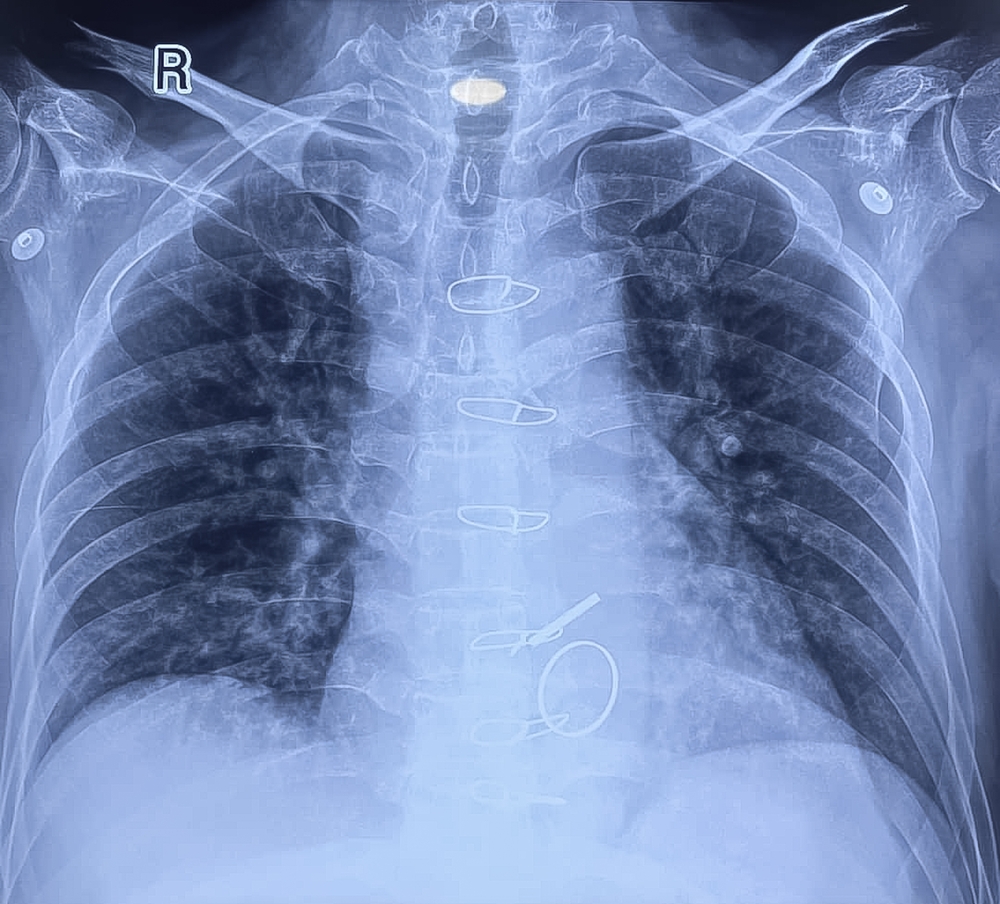

Then the X-ray confirmed it – a metal bottle cap was sitting in his upper esophagus.

It had fallen into his red Solo cup without him noticing, and he drank it down with the beer.